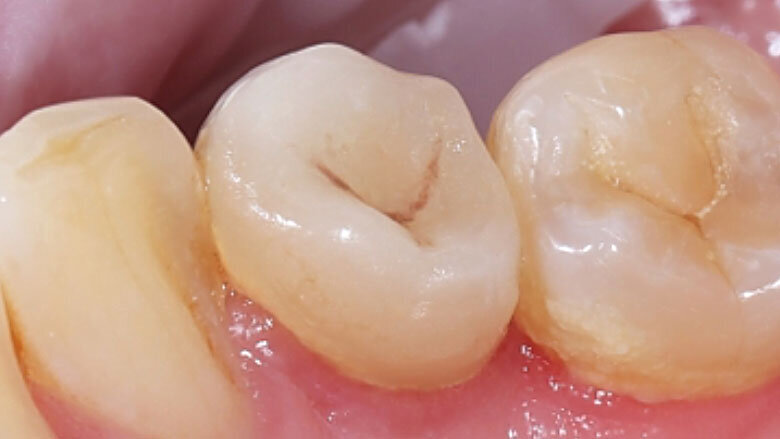

Fig. 1. Situación inicial: el diente 34 estaba fuertemente dañado. La encía se había adentrado en la cavidad.

Una paciente de 48 años acudió a la clínica porque el diente 34 se le había fracturado y otro odontólogo le había sido previamente que no se podía salvar. Durante el examen clínico se observó un defecto distooral muy extendido. La encía se había adentrado en la cavidad. La radiografía reveló una obturación insuficiente del canal radicular. Dado que una preparación de corona completa habría provocado una pérdida de las zonas de pared vestibulares y mesiales del diente, se decidió realizar una endocorona con VITABLOCS Mark II. Tras la gingivectomía, se reconstruyó el diente 34 con composite mediante láser y se llevó a cabo un tratamiento de revisión.